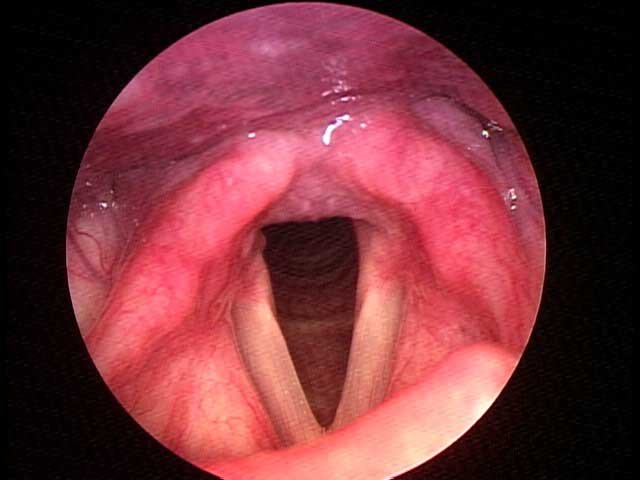

Paquidermia interaritenoidea y pequeño granuloma posterior derecho en una paciente con reflujo faringo-laríngeo.

Los pacientes pueden presentar paquidermia o hipertrofia de la mucosa interaritenoidea, edema y eritema de esta zona, abundante cantidad de moco espeso, granulomas o úlceras de contacto y edema de los pliegues vocales, entre otros.